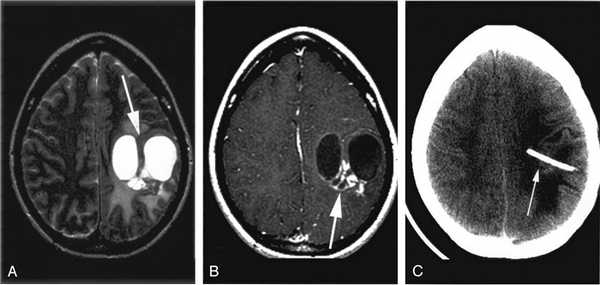

Пациентке была выполнена МРТ основания черепа по описанной методике (рис. 1). Рисунок 1. МРТ основания черепа больной Ф. с хроническим правосторонним гнойным средним отитом. Фистула лабиринта. Холестеатома. а — исследование в режиме Т1; б — в режиме Т2; в — в режиме non-EPI DWI.

В режиме Т1 справа определяется образование с низкой интенсивностью сигнала, а в режиме Т2 и non-EPI DWI — образование с гиперинтенсивным сигналом. Диагноз: хронический правосторонний гнойный средний отит; холестеатома; фистула лабиринта. Пациентка была подвергнута санирующей операции на правом ухе с тимпанопластикой и облитерацией паратимпанальных пространств. Были выявлены холестеатома, заполняющая аттик, адитус, антрум, деструкция цепи слуховых косточек, фистула латерального полукружного канала. Послеоперационный период протекал без особенностей, на 15-е сутки была удалена гемостатическая губка и силиконовая выстилка. При контрольном осмотре ухо сухое, отмечает улучшение слуха, головокружения нет. Через 12 мес проведено повторное МРТ-исследование. Признаков холестеатомы не обнаружено. Получен хороший функциональный результат — ухо толерантно к воде, самоочищается.

На КТ височных костей справа послеоперационная полость, заполненная мягкотканным образованием, определяется большой костный дефект в направлении сигмовидного синуса и мозжечка (рис. 2, а). Рисунок 2. КТ и МРТ височных костей больной У. с хроническим правосторонним средним отитом. Состояние после радикальной операции (1993 г.), санирующей операции с мастоидопластикой и тимпанопластикой (2003 г.). Холестеатома. Парез лицевого нерва. а — КТ; б — МРТ основания черепа в режиме Т1; в — в режиме Т2; г — в режиме non-EPI DWI.

Больной была выполнена МРТ (рис. 2, б—г).

В режимах Т2 и non-EPI DWI определяется сигнал высокой интенсивности, в режиме Т1 — низкоинтенсивный сигнал. Это может свидетельствовать о наличии холестеатомы мастоидальной полости и пирамиды височной кости. Диагноз: хронический правосторонний средний отит; состояние после радикальной операции в 1993 г. и санирующей операции с мастоидопластикой и тимпанопластикой в 2003 г.; холестеатома; парез лицевого нерва.

На КТ правой височной кости определяется затемнение в области аттика и антрума, цепь слуховых косточек сохранена (рис. 3, а). Рисунок 3. КТ и МРТ височных костей больного А. с адгезивным средним отитом справа, фиброзной облитерацией аттика. а — КТ; б — МРТ основания черепа в режиме Т1; в — в режиме Т2; г — в режиме non-EPI DWI.

Пациенту выполнена МРТ основания черепа по описанной методике (рис. 3, б—г).

В режиме Т1 и Т2 справа определяется очаг с высокой интенсивностью сигнала, тогда как в режиме non-EPI DWI патологических образований не выявлено. Диагноз: адгезивный средний отит справа, фиброзная облитерация аттика.